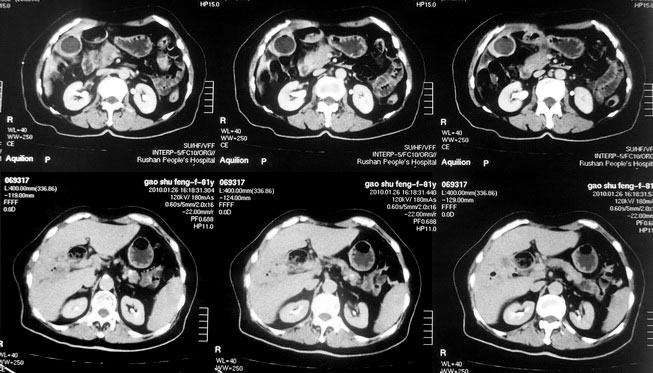

女,80岁既往有胆系手术史。近2月出现食欲不振,近20天出现畏寒发热,体重约下降10kg,体温一般在38℃左右。血常规wbc正常,中性比例88%,cea 10.3,afp、ca199均正常。做过一次肝穿,抽出约3ml仿佛脓性液体。这是她的增强ct扫描,请大家帮帮忙。另外想问问肝脓肿和胆管细胞癌的ct表现有什么区别。谢谢了。

【湘江一滴】化脓性胆囊炎及胆管炎,肝内胆管积气、积液、扩张;胆囊壁增厚、强化;胆周积液。未见肝内占位征象。

【shuiyuan】化脓性胆囊炎及胆管炎,肝内胆管积气、积液、扩张;胆囊壁增厚、强化;胆周积液.

肝脓肿动脉期呈明显环形强化或蜂窝状强化,胆管细胞癌动脉期强化不明显,且伴肝内胆管扩张。

【zenxisengming 】肝内胆管扩张积气,胆囊比环形增厚,胆囊周围渗出,未见占位性病变,应该是胆道化脓性感染

【sunbin】肝内见多个气体密度影伴气液面,胆囊壁增厚,胆囊周围低密度环绕,未见强化,支持化脓性胆管炎、胆囊炎。

最近复查ct,做了第二次穿刺抽脓,顺便做了涂片病理活检,结果找到恶性肿瘤细胞,诊断肝癌合并肝脓肿。看来大家都走眼了啊。